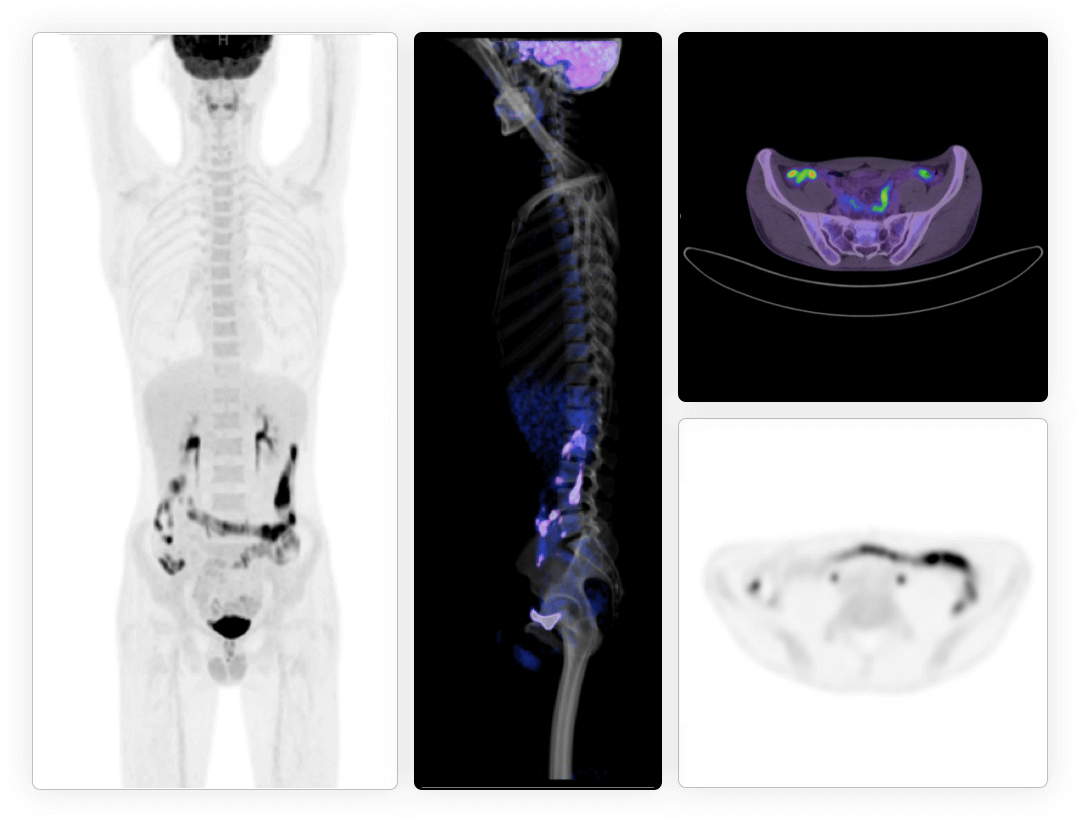

兼顾噪声、对比度、分辨率等多维度进行分布渐进式学习优化

多个神经网络嵌入迭代重建中,加速图像收敛

极低噪声、高对比度uEXPLORER海量优质图像训练集有效保证输出结果的可靠性

*uExcel DPR仅供科研使用

同时实现图像对比度、噪声、信噪比三重优化